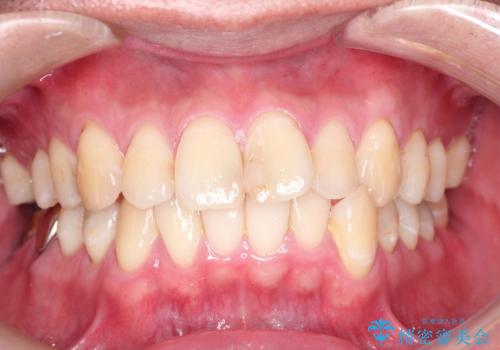

30代女性 前歯のがたつき